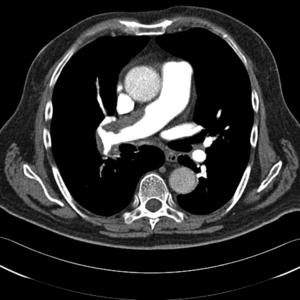

Zakrzepowo-zatorowe nadciśnienie płucne to nadciśnienie płucne spowodowane mechanicznym zamknięciem łożyska płucnego przez zorganizowane skrzepliny. Najczęściej jest to niekorzystne zejście epizodu ostrej zatorowości płucnej nazywane przewlekłą zatorowością płucną, a nie pierwotna in situ zakrzepica naczyń płucnych, chociaż w CTEPH klasyczne czynniki ryzyka żylnej choroby zakrzepowo-zatorowej występują rzadko [3]. Według definicji z aktualnych wytycznych Europejskiego Towarzystwa Kardiologicznego z 2009 r. CTEPH należy rozpoznawać przy współistnieniu przedwłośniczkowego nadciśnienia płucnego (średnie ciśnienie w tętnicy płucnej ≥25 mm Hg, ciśnienie zaklinowania w tętnicy płucnej ≤15 mm Hg, naczyniowy opór płucny >2 j. Wooda) i stwierdzeniu w badaniach obrazowych przewlekłych/zorganizowanych zawężających skrzeplin w sprężystych tętnicach płucnych [4]. Zwykle uważa się, że warunkiem rozpoznania CTEPH jest wykrycie przynajmniej jednego segmentalnego defektu perfuzji płucnej w scyntygrafii perfuzyjnej, tomografii komputerowej lub arteriografii tętnicy płucnej.

Zwykle pierwsze podejrzenie PH stawia się na podstawie wyniku badania echokardiograficznego, gdy szacowana wysokość skurczowego ciśnienia w tętnicy płucnej (systolic pulmonary artery pressure, SPAP) na podstawie pomiaru maksymalnej prędkości fali niedomykalności trójdzielnej przekracza 50 mm Hg. Wykrycie innych cech PH, jak powiększenie prawej komory, objawy jej przeciążenia z zaburzeniem geometrii ruchu przegrody międzykomorowej czy nieprawidłowy charakter spektrum doplerowskiego wyrzutu do tętnicy płucnej, skłania do rozważenia rozpoznania PH już przy wartościach SPAP >36 mm Hg [4]. Przy podejrzeniu PH niezbędna jest pełna diagnostyka, w tym echokardiografia przezprzełykowa i badanie z kontrastem w celu poszukiwania ewentualnego przecieku wewnątrzsercowego.

Klasyczne badanie radiologiczne klatki piersiowej nie rozstrzyga o rozpoznaniu, szczególnie we wczesnym okresie choroby. Wraz z postępem PH poszerza się jednak pień i główne gałęzie tętnic płucnych, a także obserwuje się cechy powiększenia prawej komory serca. Obecność obszarów beznaczyniowych w porównaniu z resztą pól płucnych może budzić podejrzenie CTEPH jako przyczyny PH.